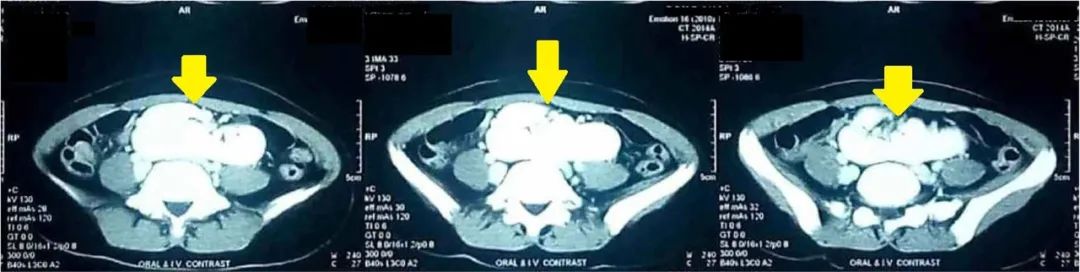

MDCT显示一个圆形肿块,大小约9 cm(垂直)×10 cm(水平),位于盆腔骶骨岬前方。该肿块最终确定为两个异位肾后外侧旋转不良,并在第三、第四和第五腰椎(L3-L5,腹主动脉分叉处下方)中线前方的内侧融合,形成了一个团块肾,能清晰显示血管供应和尿路解剖。